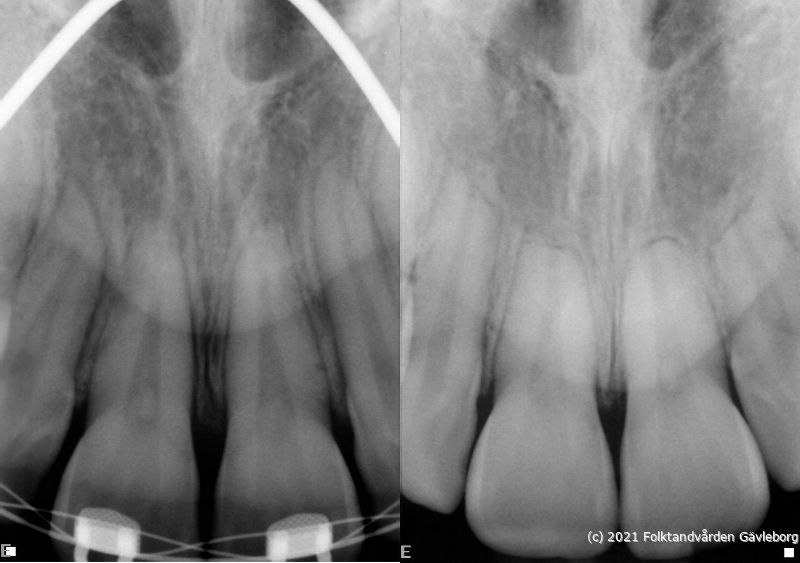

På ortodontiklinikerna diagnostiserar och behandlar vi bettfel på både barn och vuxna. Alla våra patienter kommer på remiss till oss. Vi behandlar bettfelen med fastsittande och avtagbar apparatur. Hos oss behandlas också de patienter som har avvikelser i käk- och ansiktsskelettet och som kräver tandreglering inför rekonstruktiv kirurgi. Vi har ett nära samarbete med allmäntandvård, privattandvård och övrig specialisttandvård i länet samt ett gott samarbete med Akademiska Sjukhuset i Uppsala när det gäller barn med olika syndrom och läpp-käk-gomdefekter. Våra specialistkliniker finns i Gävle och Hudiksvall.

Här nedan hittar du några exempel på vanligt förkommande behandlingar. Hittar du inget som passar det du vill visa, gå in på menyn ovan genom att föra musen över "Information". Navigera sedan till respektive apparatur. Klickar du på rubriken "Visa alla bilder" får du upp samtliga apparaturer som finns här.